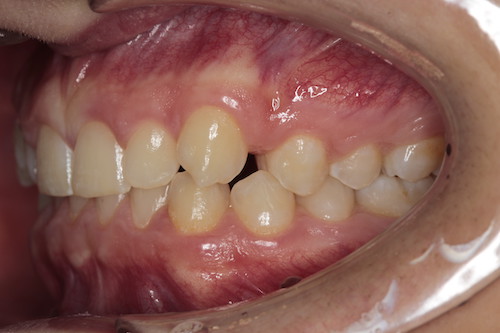

Частая ситуация, когда в общем все не плохо, но чего- то не хватает для идеала. Основной жалобой пациента было наличие выраженных промежутков на верхней челюсти, неровность положения зубов, глубокое перекрытие передних нижних резцов. Причина наличия промежутков заключалась в недостаточном размере по ширине боковых резцов верхней челюсти. именно поэтому после подъема высоты прикуса, нормализации наклонов зубов в переднем отделе, коррекции высоты перекрытия резцов, и доведение идеальных контактов в боковых отделах мы увеличили размер боковых резцов за счет композитного материала. Срок лечения 1 год.

До